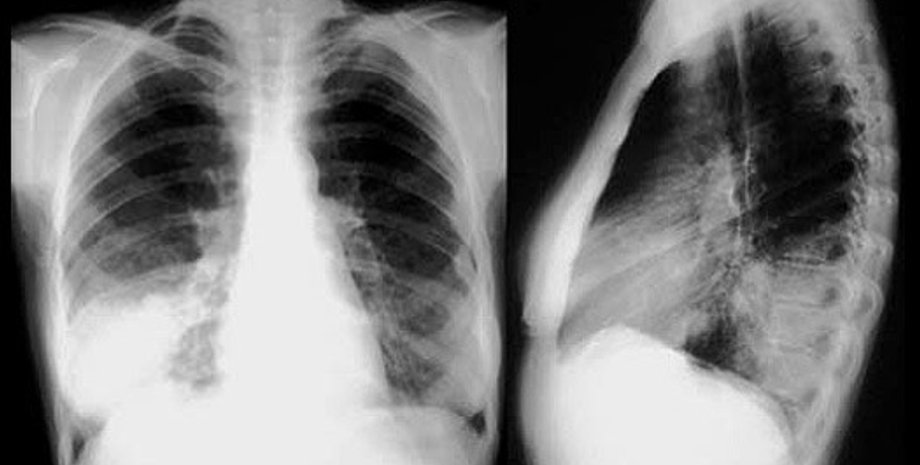

На Прикарпатье пневмония унесла еще 5 жизней

По ее словам, за последние сутки в регионе умерли 5 человек, среди которых 19-летняя женщина, родившая вчера ребенка. Ребенок жив, сообщает УНИАН.

Также Цихонь сообщила, что есть случаи, когда заболевшие умерли, лечась от пневмонии. Но их смерть наступила из-за сопутствующих заболеваний, которые и осложнили их состояние.